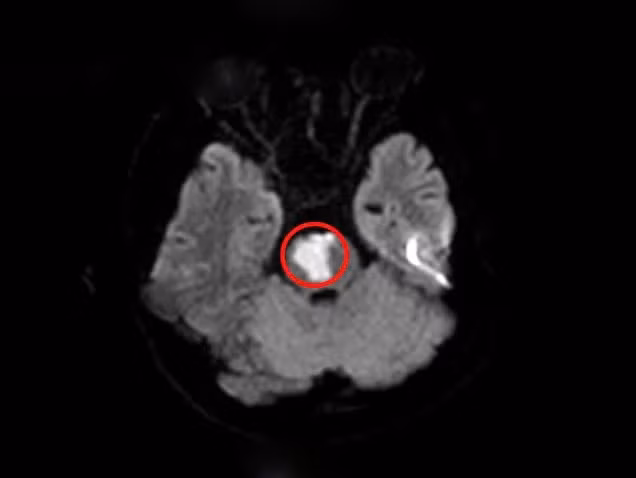

Sau khi tiến hành chụp MRI sọ não, kết quả cho thấy người bệnh có khối nhồi máu tiểu não, cầu não do tắc động mạch thân nền. Trên kết quả xét nghiệm máu có rối loạn lipid máu, một yếu tố nguy cơ dẫn đến các vấn đề tim mạch và mạch máu não.